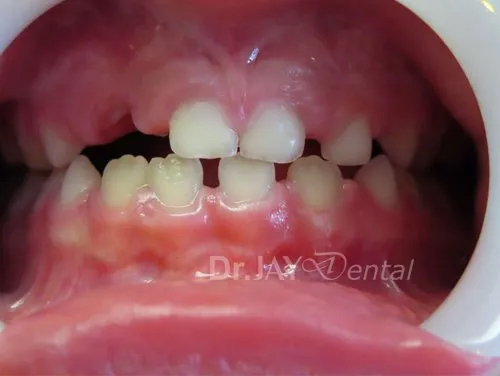

Patient had issue with spacing needed for erupting teeth , patient still going through treatment. After picture : in 6 months with Myofunctional therapy and tongue tie revision , jaws are widening and teeth are having space to erupt

Before

After